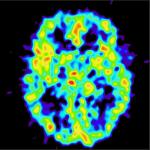

Endorphins are neurotransmitters in the brain that, when paired with their receptors, can block pain and also stimulate a feeing of pleasure, thus, the “runners’ high” and other sources of pain and stress.